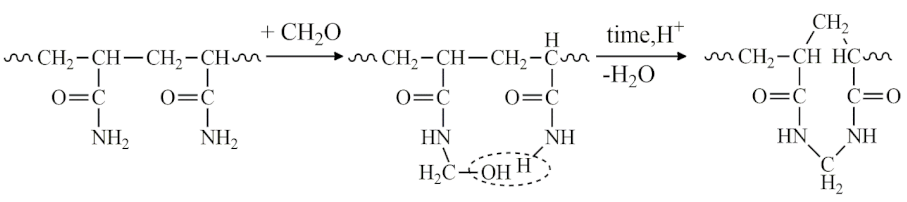

- MG-23: Gel implanted in the mammary glands for 23 years.

- LB-27: Gel from the left breast implanted for 27 years (contains dense infiltrate inclusions).

- RB-27: Gel from the right breast implanted for 27 years.

- MG-23: Gel implanted in the mammary glands for 23 years.

- LB-27: Gel from the left breast implanted for 27 years (contains dense infiltrate inclusions).

- RB-27: Gel from the right breast implanted for 27 years.